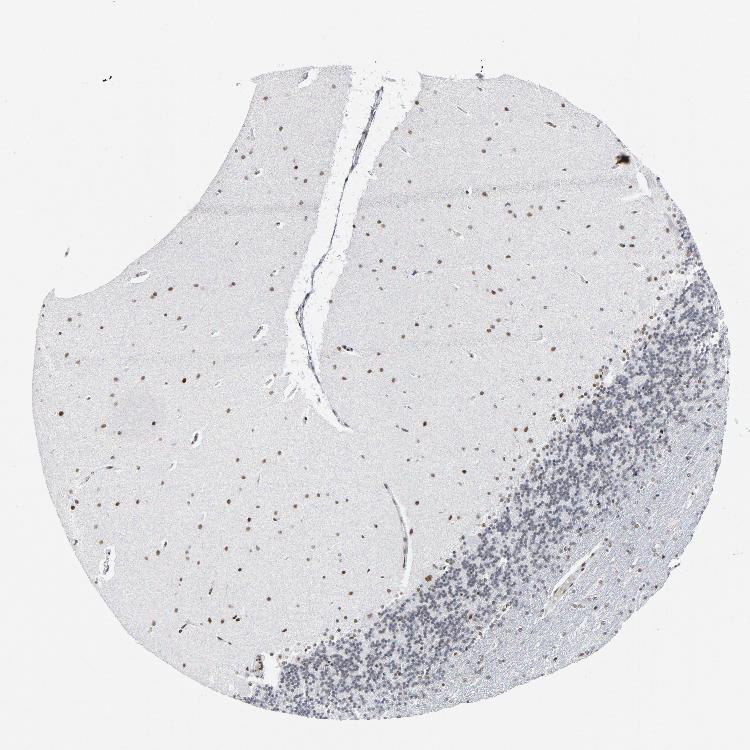

BRAIN CEREBELLUM Show tissue menu

CEREBELLUM - Expression summary

Protein expression

Cerebellumi

On the top, protein expression in current human tissue, based on all annotated cell types, is reported with the units not detected (n), low (l), medium (m) and high (h). Underneath, protein expression in each annotated cell type are reported using the same units.

Protein expression data is based on knowledge-based annotation. For genes where more than one antibody has been used, a collective score is set.

If knowledge-based annotation could not be performed for a gene, no data is displayed here. View antibody staining data further down this page.

Cells in granular layer: Low

Cells in molecular layer: High

Purkinje cells: High

CEREBELLUM - Antibody stainingi

Antibody staining in the annotated cell types in the current human tissue is reported as not detected, low, medium, or high, based on conventional immunohistochemistry profiling in selected tissues. This score is based on the combination of the staining intensity and fraction of stained cells.

Each image is clickable and will lead to virtual microscopy that enables deeper exploration of all samples and also displays staining intensity scores, fraction scores and subcellular localization as well as patient and tissue information for each sample.

Antibody HPA008888Antibody CAB004239

Purkinje cells HighHigh

Cells in granular layer LowLow

Cells in molecular layer HighHigh